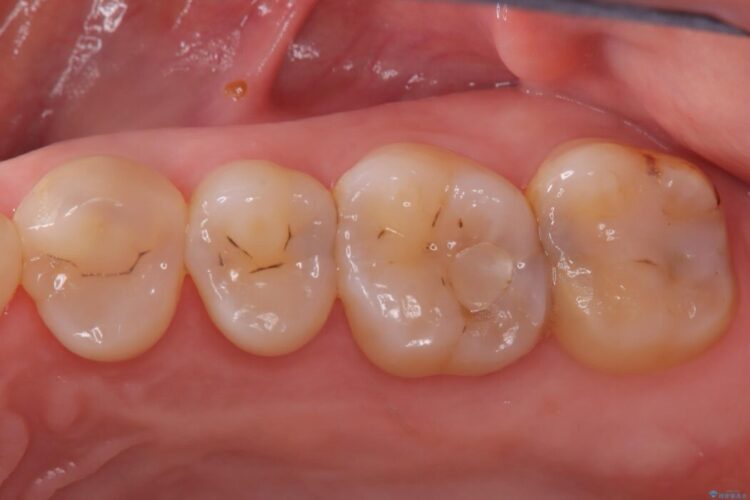

銀歯の段差の改善、ラバーダム防湿下で行うセラミックインレー治療

銀歯の段差の改善、ラバーダム防湿下で行うセラミックインレー治療 ビフォー 銀歯の段差の改善、ラバーダム防湿下で行うセラミックインレー治療 アフター

当院でメンテナンスに通われている患者様の症例です。